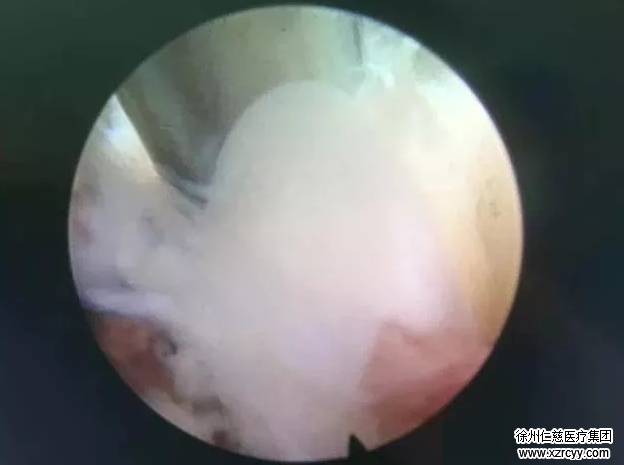

这是在内视镜下抓取椎间盘髓核:

这是取出4.2g椎间盘髓核(空袋重1.0g):